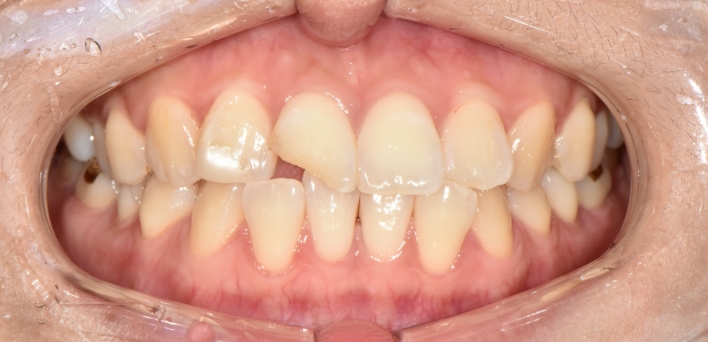

우리 얼굴에서 미소는 첫인상을 좌우합니다. 이런 좋은 인상을 위해 라미네이트를 고려 중이시라면,

많은 것들을 고려해야 합니다. 라미네이트 시 무조건 하얗고, 얇기만 한 치아가 좋은 것은 아닙니다.

개개인의 얼굴마다 비율에 맞게 이상적인 치아의 형태가 있습니다.

더서울치과의원은 정확한 안모 분석을 통한 프로파일 예측 치료로 심미성은 물론 치아 본연의 기능 회복까지 가능하도록

안면 근육과 기능, 치아 형태, 비율, 크기, 교합, 색감 등 전반적인 비율을 맞추어 본인에게 잘 맞는 치아의 형태로 복원합니다.

단순하게 예쁘고, 심미적으로 만드는 인위적인 작업물이 아닌,

자연치아와 가장 유사하도록 치아를 복구하는데에 초점을 맞추어

치아복구 + 치아성형 2가지의 장점을 합쳐

개개인 손상 정도에 따른 맞춤형 보철을 제작합니다.

※ 더서울치과의원은 의료법을 준수하며 위 케이스는 실제 환자의 동의를 얻은 사례로 치료 전, 후가 동일한 환경에서 촬영되었습니다.

환자 케이스에 따라 부작용이 발생할 수 있습니다. 이 부분은 의료진의 충분한 상담과 체크를 통해 예방하고 줄일 수 있습니다.

[심미치료 부작용] 시술 후 치아 시림, 보철물 파손 등의 부작용이 발생할 수 있어 개인별 치아 상태에 따른 정확한 진단과 사후 관리가 중요합니다.